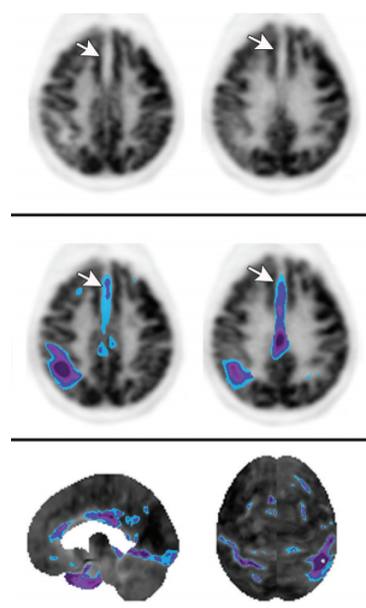

If the frontal lobe or internal capsule is involved, hypometabolism in the contralateral cerebellum may be seen due to crossed cerebrocerebellar diaschisis

atrophy –> sulcal widening –> artifact of hypometabolism (pitfall for misdiagnosis of neurodegenerative disorder)